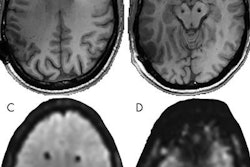

Current metal-based electrodes can produce heat and create image artifacts in MRI scans, thus blocking views of abnormalities in the brain. They also can become magnetized from the bore's magnet vibrations when patients undergo MRI scans.

A side-by-side look at platinum (left) and glassy carbon (right) thin-film electrodes for deep brain stimulation. Image courtesy of San Diego State University.SDSU and KIT researchers tested the carbon electrodes directly in an MRI scanner and confirmed that they did not become magnetized and did not irritate the patient's brain. They plan to develop the technology further and continue MRI safety tests.